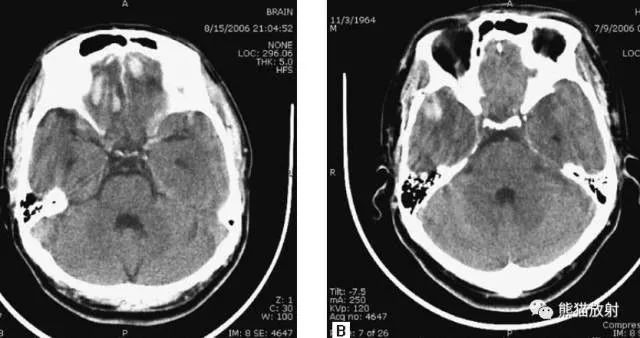

动脉瘤破裂导致蛛网膜下腔出血、

脑室积血、非交通性脑积水。

与外伤性蛛网膜下腔出血不同,动脉瘤破裂导致的SAH常不累及大脑凸面,而位于基底池附近。脑动脉瘤常位于鞍上池的Willis环血管。

A:四脑室积血;

B:中脑导水管、环池、右侧侧脑室颞角积血,前交通动脉处(动脉瘤好发位置)出血密度较高;

C:三脑室积血;

D-F:侧脑室积血,蛛网膜下腔出血(血液代替了脑脊液)。